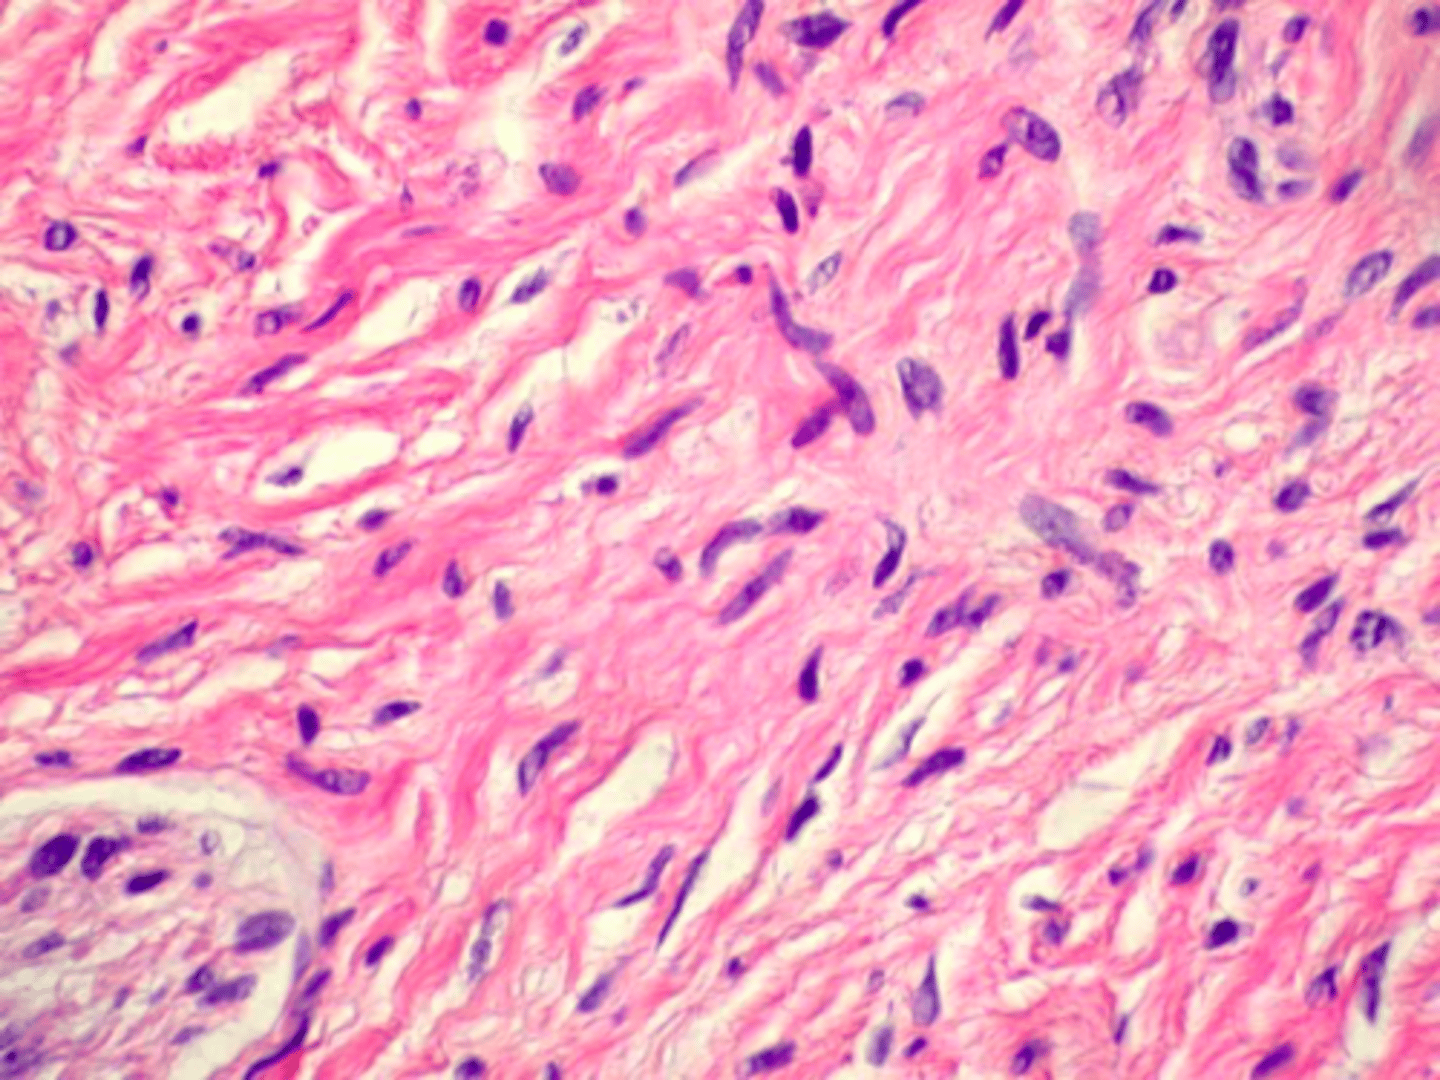

Schwannoma

Patient presents with small yellow papule on dorsal tongue. Histopathology shows microscopic circumscription and Antoni A and Antoni B histopathologic patterns. What do you suspect the oral presentation to be?